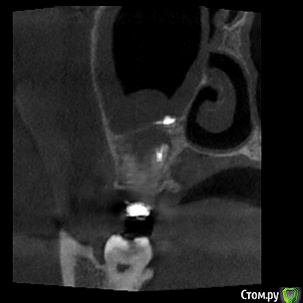

Tymchynskyi Опубликовано 2 мая, 2016 Поделиться Опубликовано 2 мая, 2016 (изменено) Пациентка обратилась по поводу периодически повторяющихся ноющих болей в области 17го зуба, постоянное ощущение дискомфорта.Месяц назад пошла на консультацию к ЛОРу где ей поставили диагноз правостороннего гайморита.Сначала баловались *кукушками* - не помогло, затем сделали прокол, и со слов пациентки, док. сказал что из пазухи исходил кариозный запах, характерный для проблемного зуба.Объективно: 16-17 зубы лечены 2г назад и покрыты МК спаянными коронками.Десневой край вокруг коронок цианотичный, нарушена БШ.В 17 зубе 3-ногая ВКВ, в 16 СВШ.Вертикальная перкуссия 17 слабо болезненная.Отправил на КТ.На буккальных апексах 16-17 и небном 17 очаги деструкции.Но больше всего интересует наличие инородного тела над апексом небного корня зуба 17(диаметр порядка 2мм).Или это артефакт??То ли обтурационный материал мигрировал вглубь пазухи, то ли ЛОР чето намудрил при вмешательстве...Что скажете?Какие прогнозы? Изменено 2 мая, 2016 пользователем Tymchynskyi Ссылка на комментарий

dantist_movani Опубликовано 2 мая, 2016 Поделиться Опубликовано 2 мая, 2016 В пазухе пломбировочный материал, опять к эндоскописту. 1.6 и 1.7 удалять. Ссылка на комментарий

DmitrySH Опубликовано 2 мая, 2016 Поделиться Опубликовано 2 мая, 2016 Пломбировочный материал в каналах на КТ сильно фонит, сложно понять что там с зубами, и сколько их осталось. Материал в пазухе проблем не должен создавать. Главное убрать источник инфекции. 3 Ссылка на комментарий